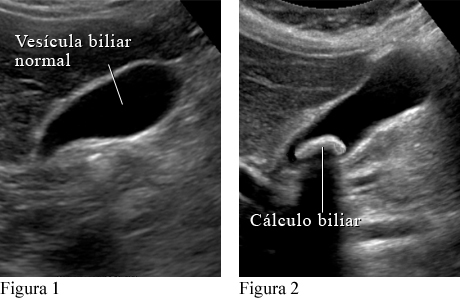

La prueba más común es una ecografía abdominal. Un auxiliar le pasa un transductor sobre el abdomen para generar imágenes en una pantalla. Pueden hacerse análisis de sangre para averiguar si los cálculos biliares están causando otros problemas graves o si los síntomas se deben a otra cosa.

Cómo se ve un cálculo biliar en una ecografía abdominal

Ecografía abdominal de la vesícula biliar

Cortesía de Intermountain Medical Imaging, Boise, Idaho.

La figura 1 muestra una vesícula biliar normal en una ecografía. La figura 2 muestra un cálculo biliar grande en la vesícula biliar.